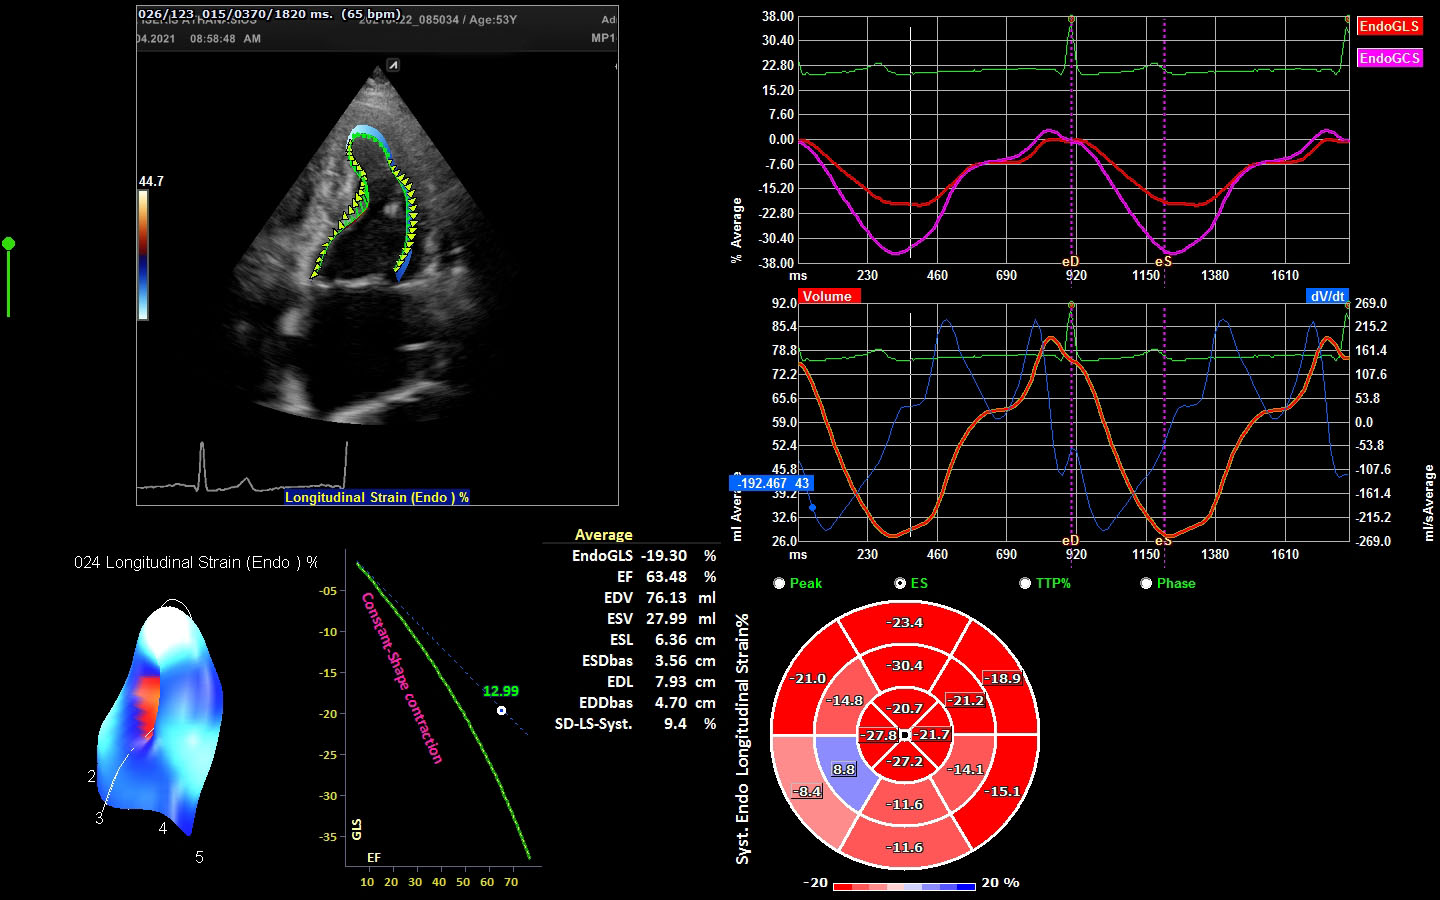

Μελέτη ιστικής παραμόρφωσης (myocardial strain)

Στο ιατρείο μας έχουμε τη δυνατόητα εφαρμογής νεότερης τεχνολογίας υπερηχογραφικών τεχνικών (longitudinal strain) που αυξάνουν κατά πολύ την διαγνωστική αποτελεσματικότητα. Το λογισμικό αναλύει την λειτουργία της καρδιάς και εντοπίζει τμηματική και συνολική δυσλειτουργία που δεν ειναι εμφανής στο γυμνό μάτι.

Εξειδικευμένη εξέταση μελέτης ιστικής παραμόρφωσης

H εξέταση γίνεται με εφαρμογή νεότερης τεχνολογίας υπερηχογραφικών τεχνικών (longitudinal strain) που αυξάνουν κατά πολύ την διαγνωστική αποτελεσματικότητα.